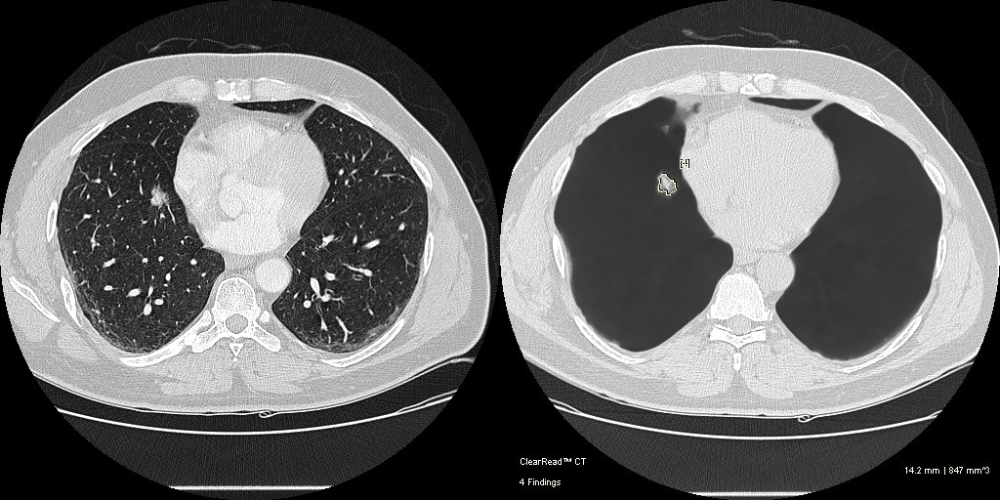

Lung cancer, emphysema, and heart disease are leading killers worldwide. Detection of these conditions is complex and time-consuming. The ClearRead™ CT cardiothoracic AI suite leverages advanced artificial intelligence for increased efficiency, improved nodule detection accuracy, and quantification of coronary artery calcification (CAC) and hypodense lung tissue*.

Vessel Suppression An unimpaired view for enhanced confidence in findings

Pulmonary Nodules Automated nodule analysis, current and prior, and reporting to lighten cognitive load

- Fully-automatic nodule detection and analysis

- Quickly & easily compare nodule findings with prior exams – monitor changes in volume, diameter, and doubling time

- Exclusive vessel suppression capability provides an unimpaired view of the chest and is approved for concurrent reading

- 36% faster reads1 and 29% fewer missed nodules2